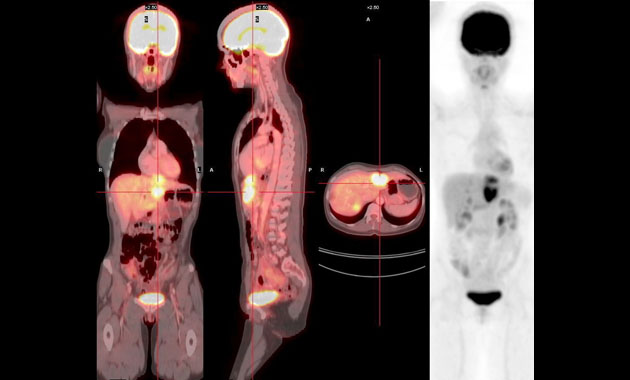

The Molecular Imaging and Therapeutics (MI&T) division, at UCSF Department of Radiology & Biomedical Imaging, oversees the clinical practice of traditional nuclear medicine, including multimodality PET/CT and PET/MR, and stewards the application of molecular therapeutic agents for our patients. The division will also work closely with the Chemistry, Probes and Molecular Therapy (CPMT) Specialized Resources Group within the department, as well as with clinicians and researchers in other departments such as oncology, cardiology and neuroscience, to usher in a new generation of imaging and treatment modalities.

- Advanced diagnostic molecular imaging modalities including new PET/CT and PET/MRI methods

- Benign and malignant tumors

- Cancers

- PET/CT